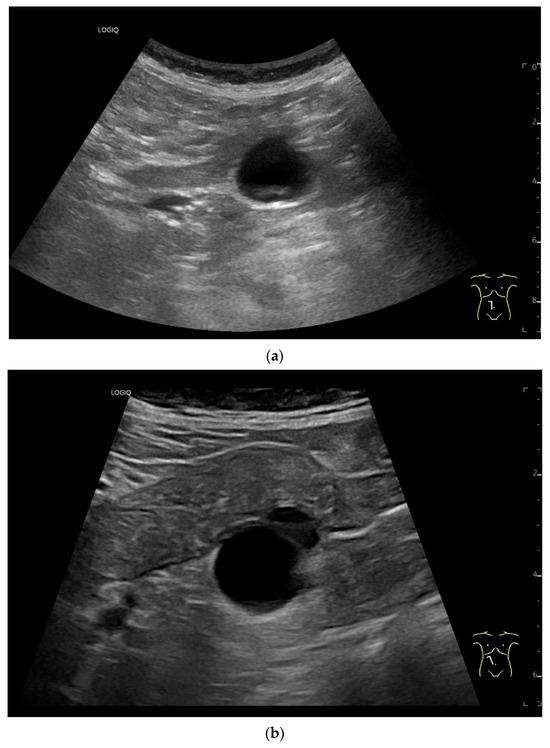

Figure 3.

Intussusception. In the ileum, the intestine is inverted. Instead of the usual five layers, there are many onion-skin-like layers (a). The intestine is folded in on itself several times. The wall is marked with arrows (b).

Figure 4.

NEN in the ileum: an approximately 14 mm hypoechoic nodular tumor is visible (a). Subsequently, peristalsis reveals a hypoechoic wall thickening (W) and hyperechoic luminal reflex (L) (b) and, finally, causes the tumor to be obscured by the luminal contents and dorsal artifacts (c). The region of the tumor is marked with a yellow arrow in all three images.